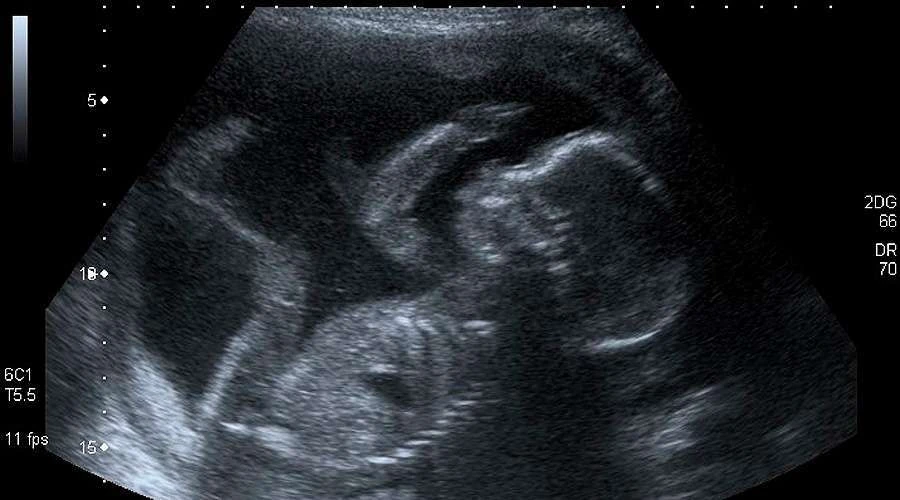

En declaraciones a ACI Prensa la Dra. Graciela Moya, que es pediatra, genetista y trabaja con médicos ecografistas, explicó que la “ecografía es un método que hace muchos años se utiliza de rutina en la clínica, sobre todo a nivel prenatal, porque es una herramienta que da muchísima información respecto de la anatomía fetal, de su ubicación, crecimiento y situación de salud”, y también “da información respecto a la mamá: de qué complicaciones podría tener”.

“Da una imagen que produce que las mamás, en general, se emocionen al ver al bebé”, aseguró.

“La ecografía lo que visibiliza es que eso que se está desarrollando en el vientre materno no es un conjunto de células, sino un ser humano que se desarrolla. Por lo tanto, lo que el médico le permite a la mujer embarazada es empezar a conocer a su propio hijo antes de su nacimiento”, resaltó.

“No nos olvidemos que en las manifestaciones provida se suele ofrecer ecografía en pantallas gigantes para que los asistentes confirmen que lo que una mujer lleva en su vientre no es un saco de células, sino un hijo gestándose”, acotó el politólogo.